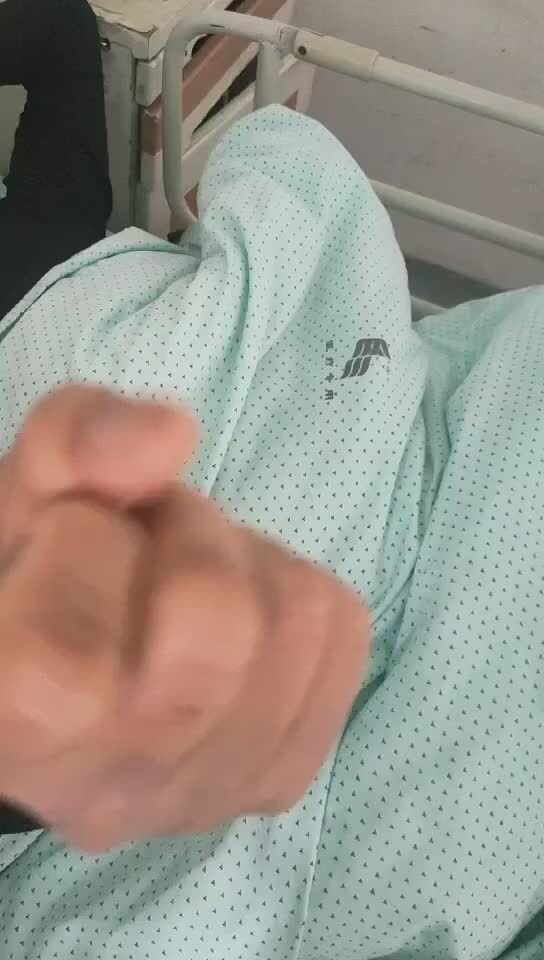

术后第二天下地走路,右手感觉、运动特别灵活,右上肢疼痛感消失,可以自己拿筷子进餐了,术后第四天康复出院。